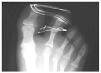

Mujer de 12 años con antecedentes personales de glaucoma congénito que acude a urgencias tras traumatismo directo en pie derecho, refiriendo dolor e impotencia funcional en el segundo dedo (fig. 1). A la exploración se observan signos inflamatorios y deformidad de dicho dedo, efectuándose la confirmación diagnóstica mediante radiología convencional anteroposterior y oblícua en la cual se aprecia luxación dorso-lateral de la articulación interfalángica proximal (figs. 2,3).

Fig. 2.—Luxación lateral en la proyección DP. Fig. 2.—Lateral luxation in dorso-plantar projection.